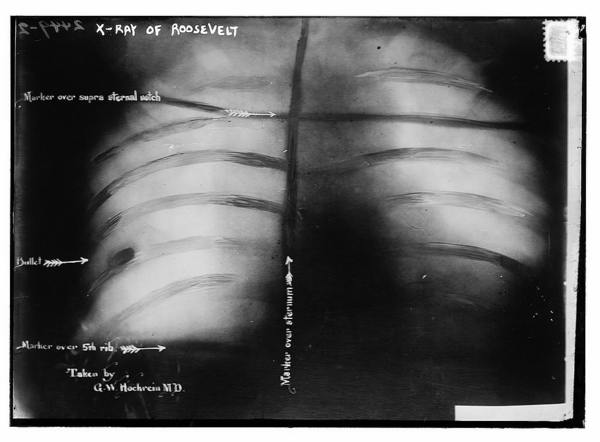

X-Ray of Roosevelt shows bullet